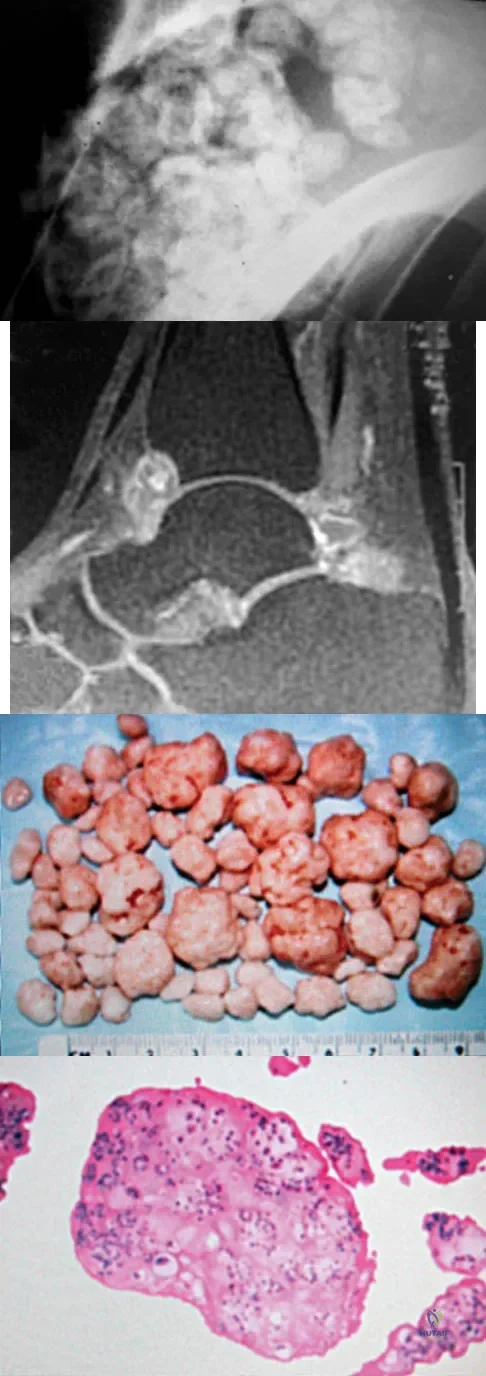

A 40-year-old man has a painful mass on his anterior ankle joint with limited range of motion. A radiograph, MRI scan, a gross specimen, and a hematoxylin/eosin biopsy specimen are shown in Figures 5a through 5d. What is the most likely diagnosis?

Explanation

Synovial chondromatosis results from chondroid metaplasia within the synovium. Male to female ratio is 2:1, with a peak incidence in early adult life. Radiographs can show speckled cal